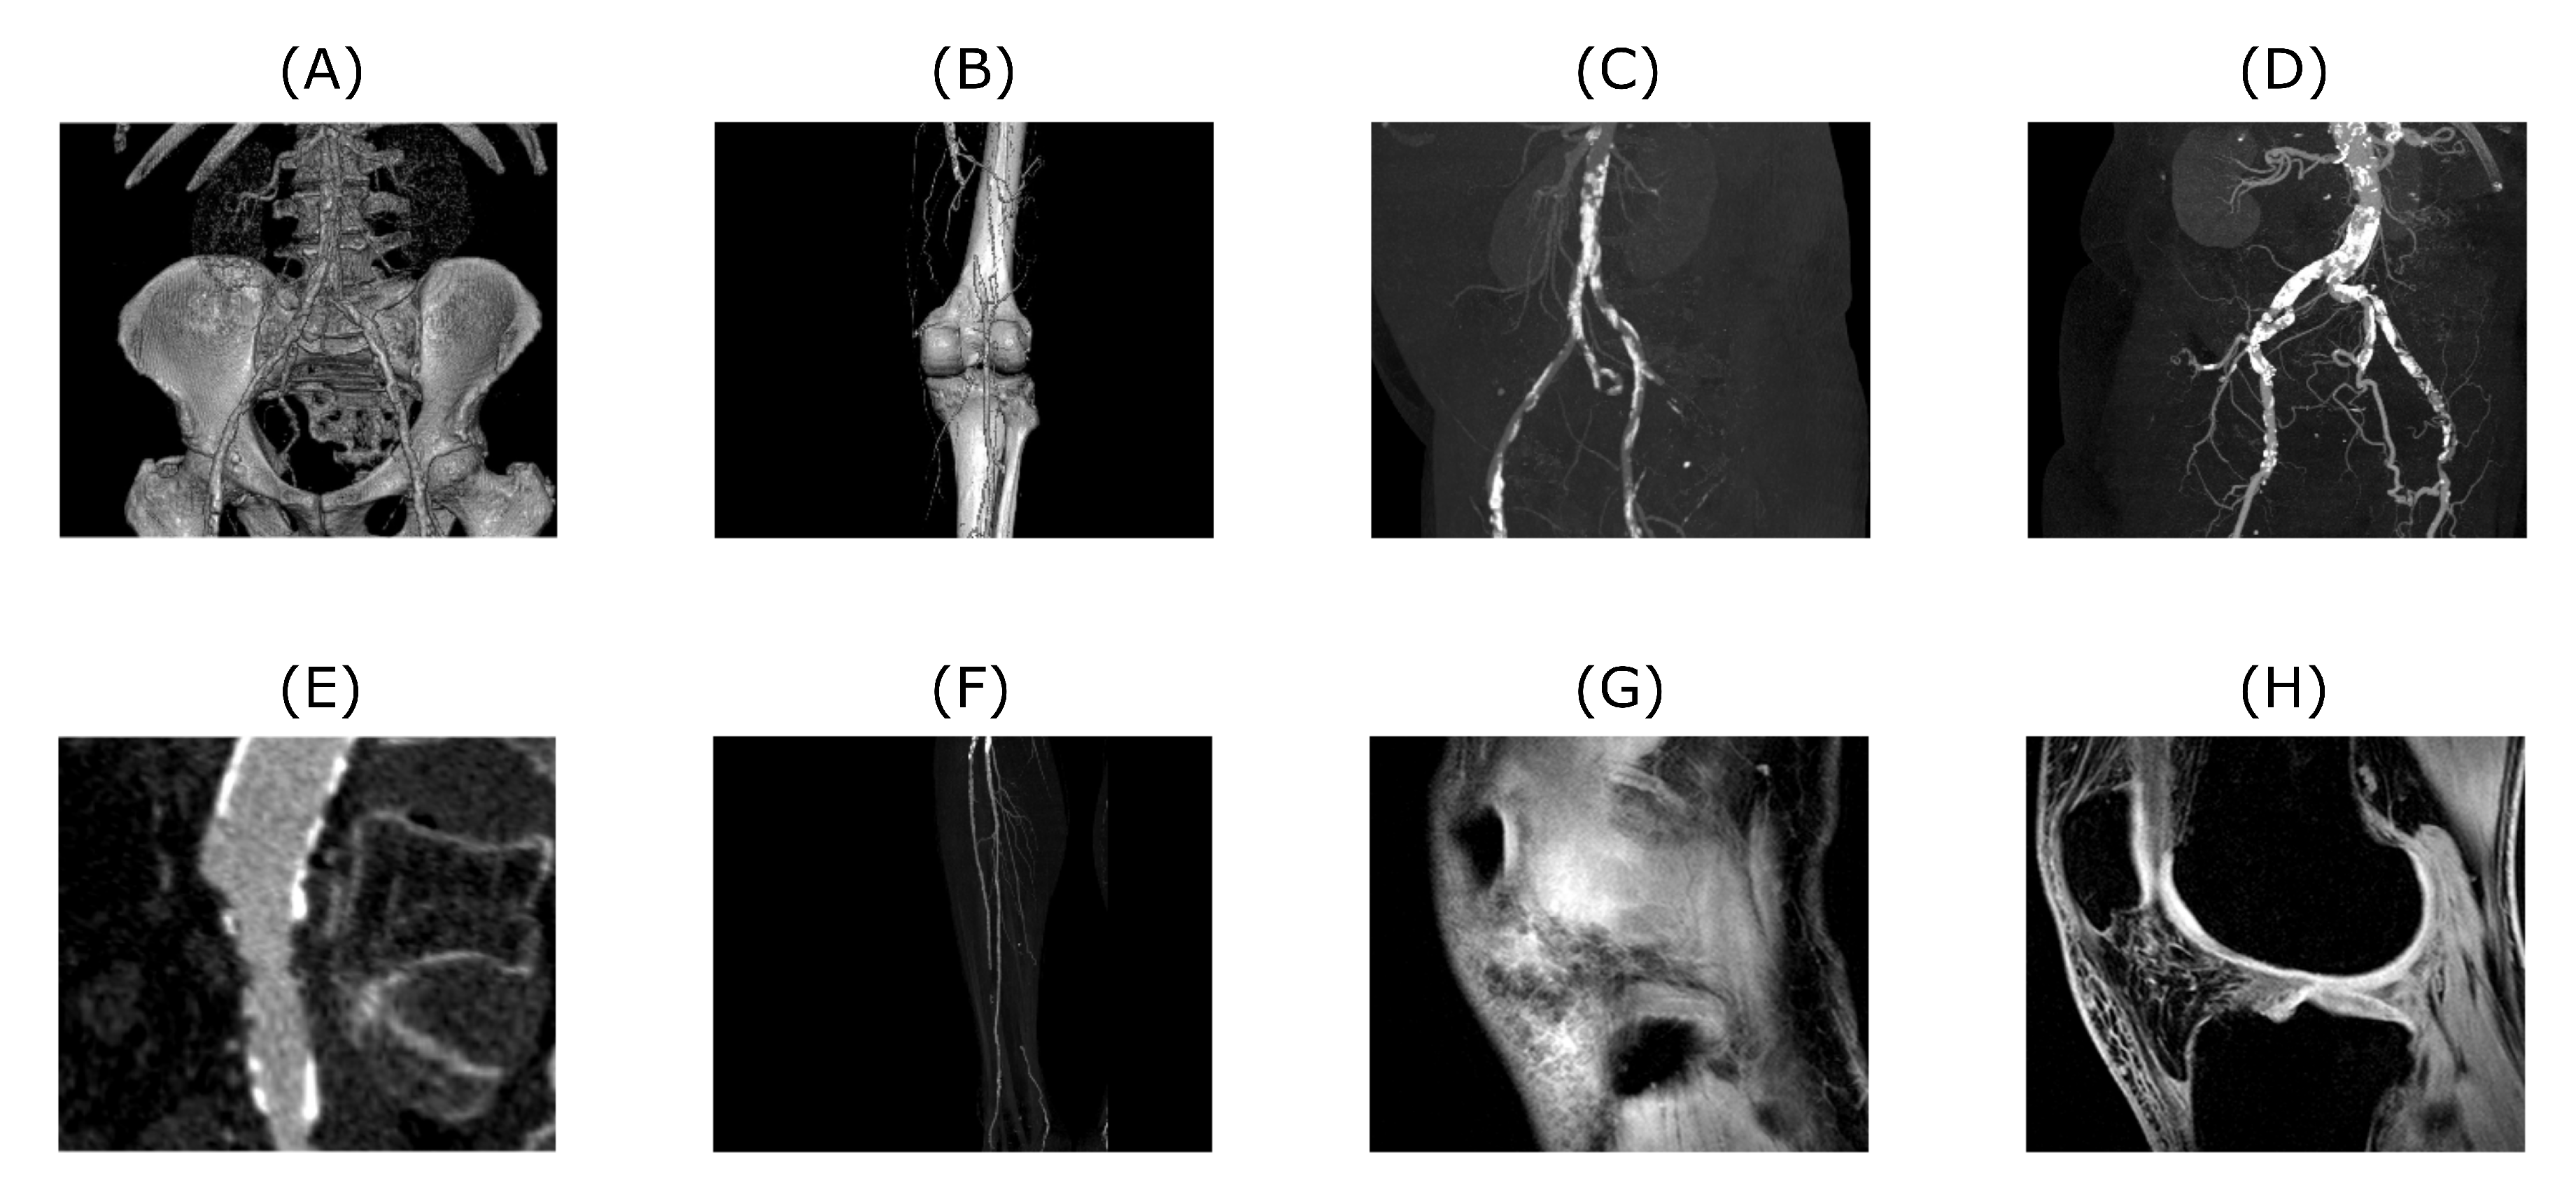

To properly analyze the performance of the approach described in the next chapter, a bank of input test data needs to be prepared and described first. In our research, we are primarily focused on the analysis of the 1D and 2D image data mostly of the musculoskeletal system. These input test data were selected to benchmark the proposed algorithm. Datasets are mostly related to the human’s musculoskeletal system, however, algorithm’s application is not limited to this specific field. As for 1D signals we used EMG measurements of hand movements from publicly available data source [56]. The algorithm’s performance of 2D datasets was tested on CT and MRI scans. CT scans are showing blood vessel calcification in the area of lower limbs. There are several levels of detail magnification so images with different properties like spatial frequency could be tested. MRI dataset is consisting of successive slices showing knee cartilage in order to test various spatial frequency images. Examples of various musculoskeletal images used for the analysis are depicted in Figure 1.

Figure 1.

Examples of CT (A–F) and MRI (G and H) scans used to test the proposed algorithm. Tested images are showing various level of magnification and amount of detail. Also, native noise levels contained within these images are different. Images (A–F) are depicting blood vessel calcification in different details and perspectives, whereas images (G–H) are showing successive slices of knee cartilage.